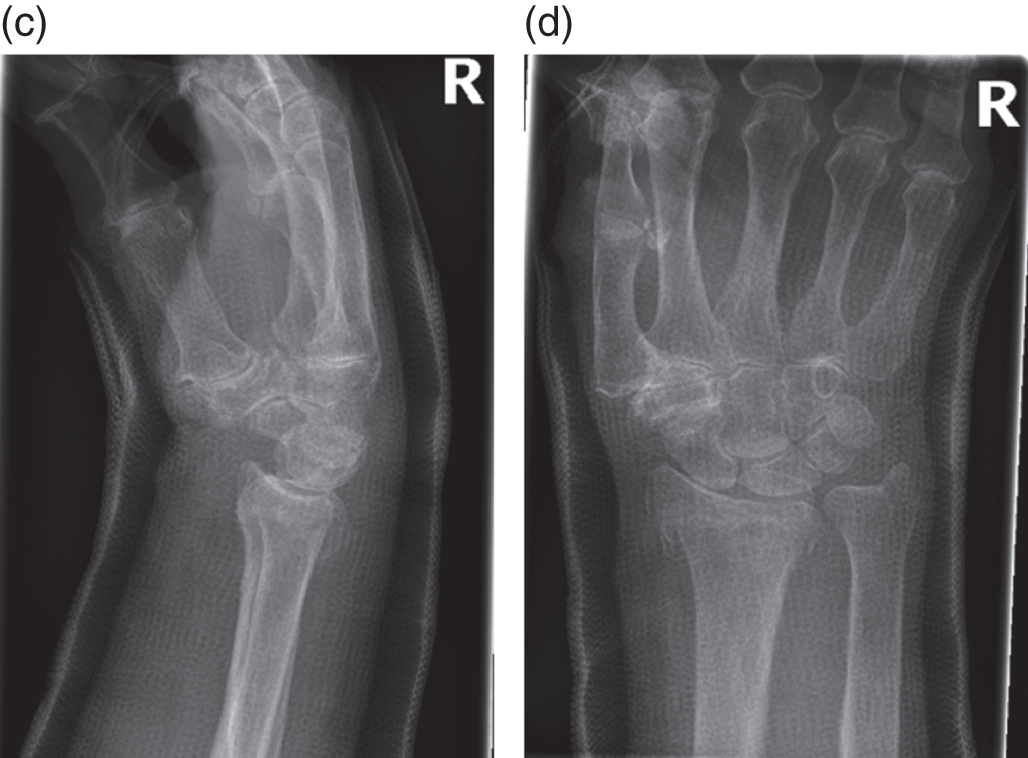

Floor shortening of the scaphoid bone. The lunate is triangular in shape outlined area as it has slipped into a dorsal intercalated segment instability disi position. Thus it is essential to identify this finding on. The scaphoid bone is one of the carpal bones of the wrist it is situated between the hand and forearm on the thumb side of the wrist also called the lateral or radial side. There is shortening of the scaphoid on the pa view with an obvious cyst fig.

Figure 1 shows radiographs of a scaphoid waist fracture with delayed union. If you press with your finger deep into the floor of the anatomic snuffbox you can barely feel the scaphoid. Once significant radiocarpal or intercarpal arthrosis has developed because of a scaphoid nonunion it is difficult to decide which treatment to adopt. The scaphoid bone is vulnerable to fracture because of its position within the wrist and its role in wrist function.